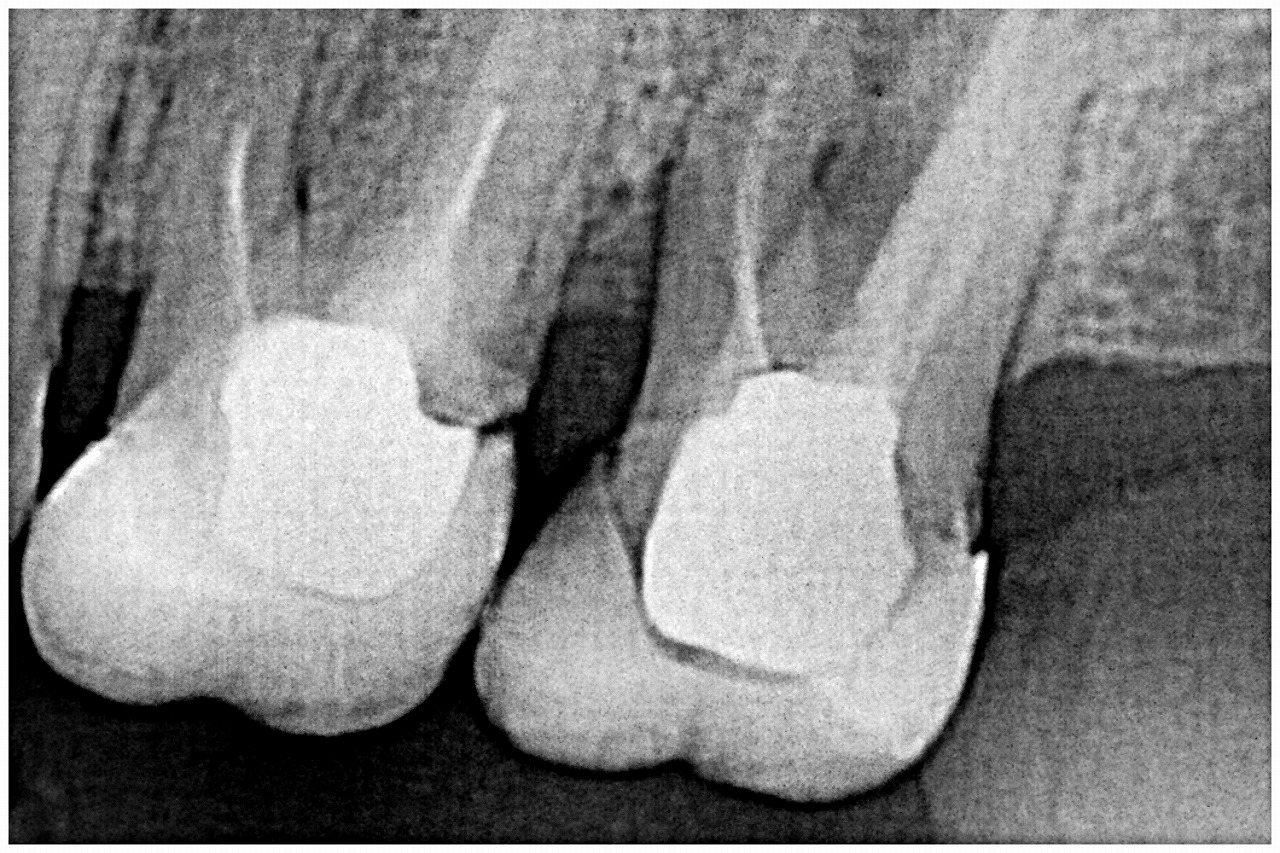

問題の左上の最期臼歯部になります

大きく破折しています

デンタルレントゲンになります

分岐部に至るまで大きく骨吸収が存在

破折が疑われます